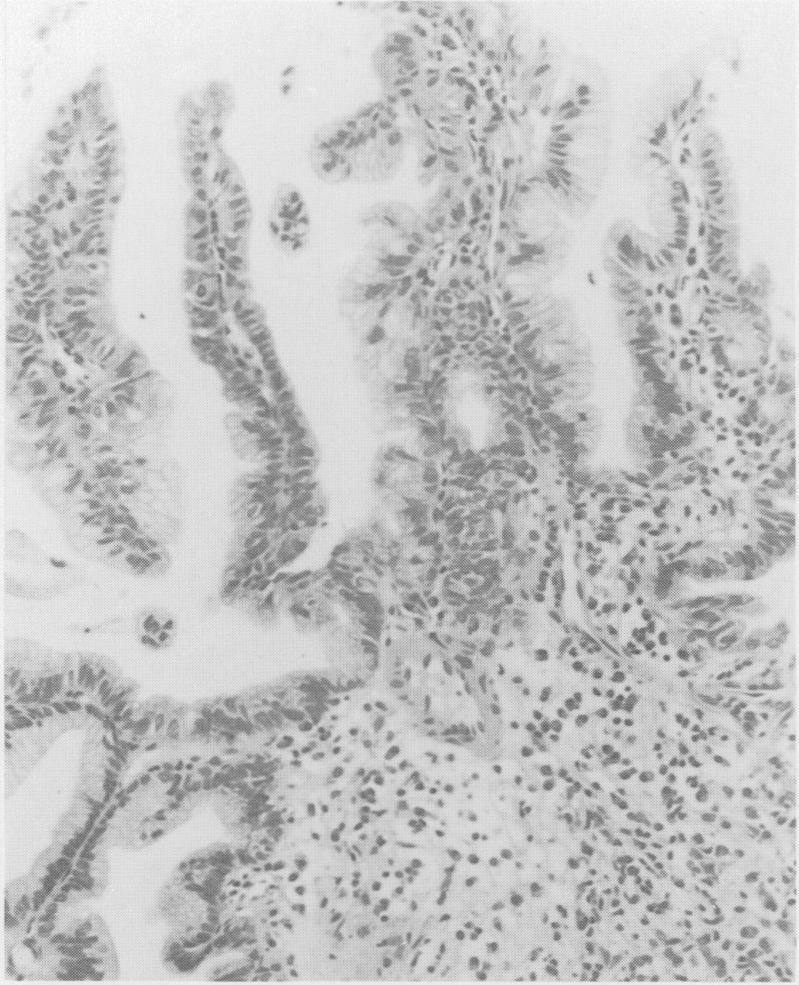

A case of villous adenoma of the common hepatic duct causing obstructive jaundice, where the diagnosis was made by ultrasound guided percutaneous biopsy is reported. At surgery ultrasonography was used to define the extent and operability of the tumour.

报告了一例肝总管绒毛状腺瘤导致梗阻性黄疸的病例,该病例通过超声引导下经皮活检作出诊断。手术时,超声检查用于确定肿瘤的范围和可切除性。